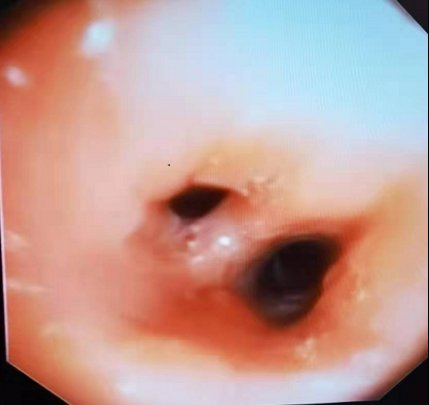

▲右中叶辣椒嵌顿冻取术

经过与患者充分沟通,并积极完善术前准备后,主治医生隋雪梅对其进行了气管镜检查。术中发现患者右中叶开口有异物嵌顿并堵塞管腔,局部肉芽组织增生,管腔严重狭窄,随即使用二氧化碳冷冻探头对异物进行了冷冻取出。